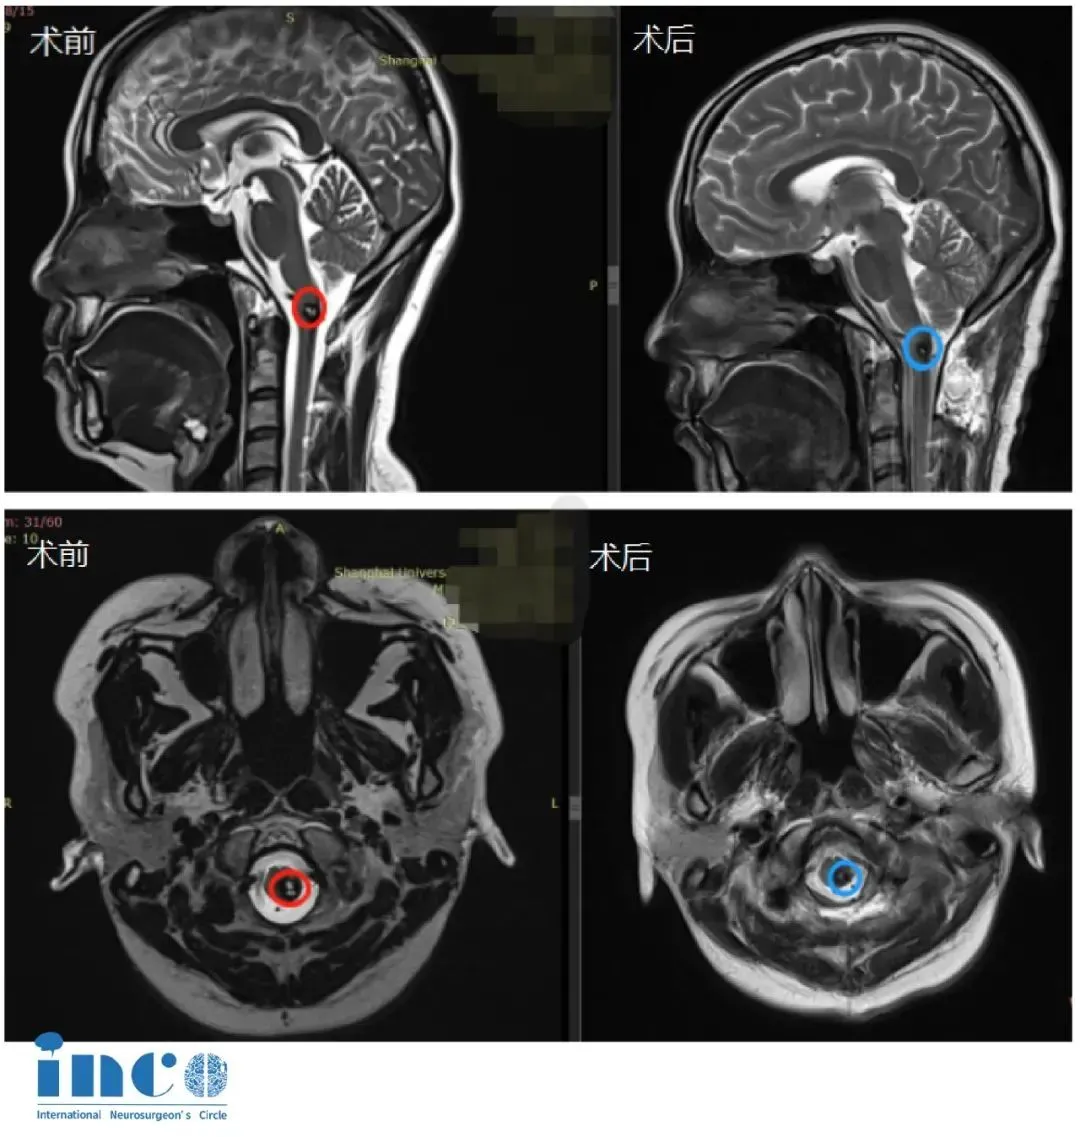

2016年,王女士开始被剧烈头痛折磨,让她彻夜难眠。家人带着她辗转多家知名医院,最终确诊为“延颈髓交界区海绵状血管瘤”。保守治疗已无法阻挡病情恶化:头痛持续加剧、四肢逐渐无力,MRI提示血管瘤随时可能再次出血,威胁生命。

2021年5月13日,作为此次手术的主刀,巴教授在术前进行了认真细致的准备。术中,巴教授在国内神经外科专家的密切配合下,凭借丰富的手术经验,避开颅内丰富的血管和神经,清晰地暴露出脑干部位的病变,最终为王女士顺利全切了海绵状血管瘤。

术后两周,王女士顺利出院。术后MRI明确显示:延颈髓交界处的海绵状血管瘤已完全切除。